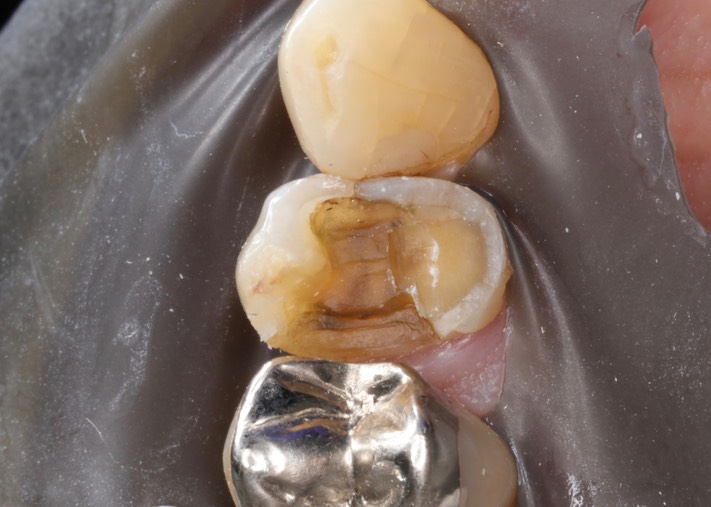

Mark Chun #12 amalgam removal